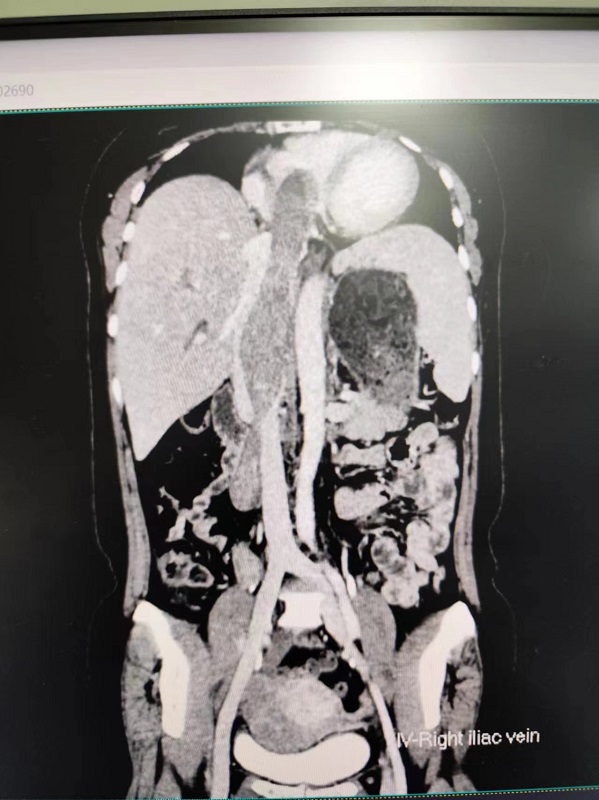

48岁的万女士,因“子宫肌瘤剥除术后3年,再次发现子宫肿块7月”来到湘雅三医院妇科就诊。患者以为只是进行一次普通的子宫肌瘤治疗,因此在住院期间心态相当轻松。然而,在完善术前检查时,却意外发现自己罹患了一种罕见疾病——静脉内平滑肌瘤病。这种疾病的特殊之处在于,子宫肌瘤沿着卵巢静脉一路向下腔静脉甚至右心房蔓延,因此又被形象地称为“长向心脏的爬山虎”。尽管其组织学表现为良性,却具有一定的生物学侵袭性。临床表现缺乏特异性,一旦病情严重,肌瘤可长满心脏,导致充血性心力衰竭、胸痛,甚至可能引发肺动脉栓塞,乃至猝死。

3月27日,麻醉科周治明副主任医师、李季主治医师全程保驾护航,妇科曾飞主任医师、潘琼副主任医师以及血管外科姚凯副主任医师、王征副主任医师轮番施术。虽然手术过程中困难层出不穷,但专家们始终保持着沉着冷静的态度,有条不紊地应对挑战。团队配合默契,手术最终顺利完成。医生们精准地切除了万女士布满肿瘤的子宫及双附件,从下腔静脉中取出了一长25cm、宽约3.5cm的瘤体。为解决用血难题,麻醉科在手术中应用了自体血回输技术,既规避了同种免疫和输血传播疾病的风险,又有效缓解了血源紧张的状况。